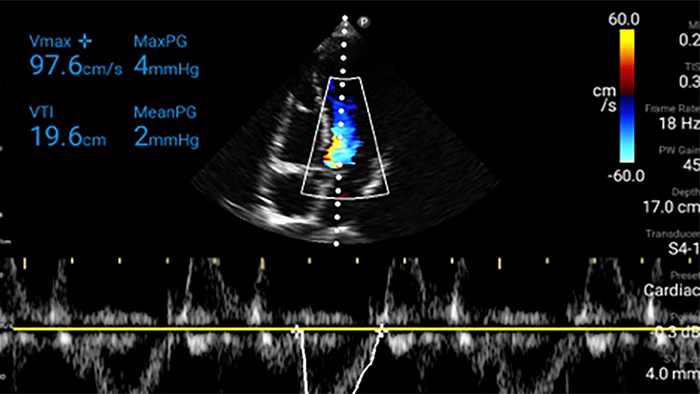

Exceptional ultrasound imaging

Lumify handheld ultrasound offers images that enhance diagnostic confidence.